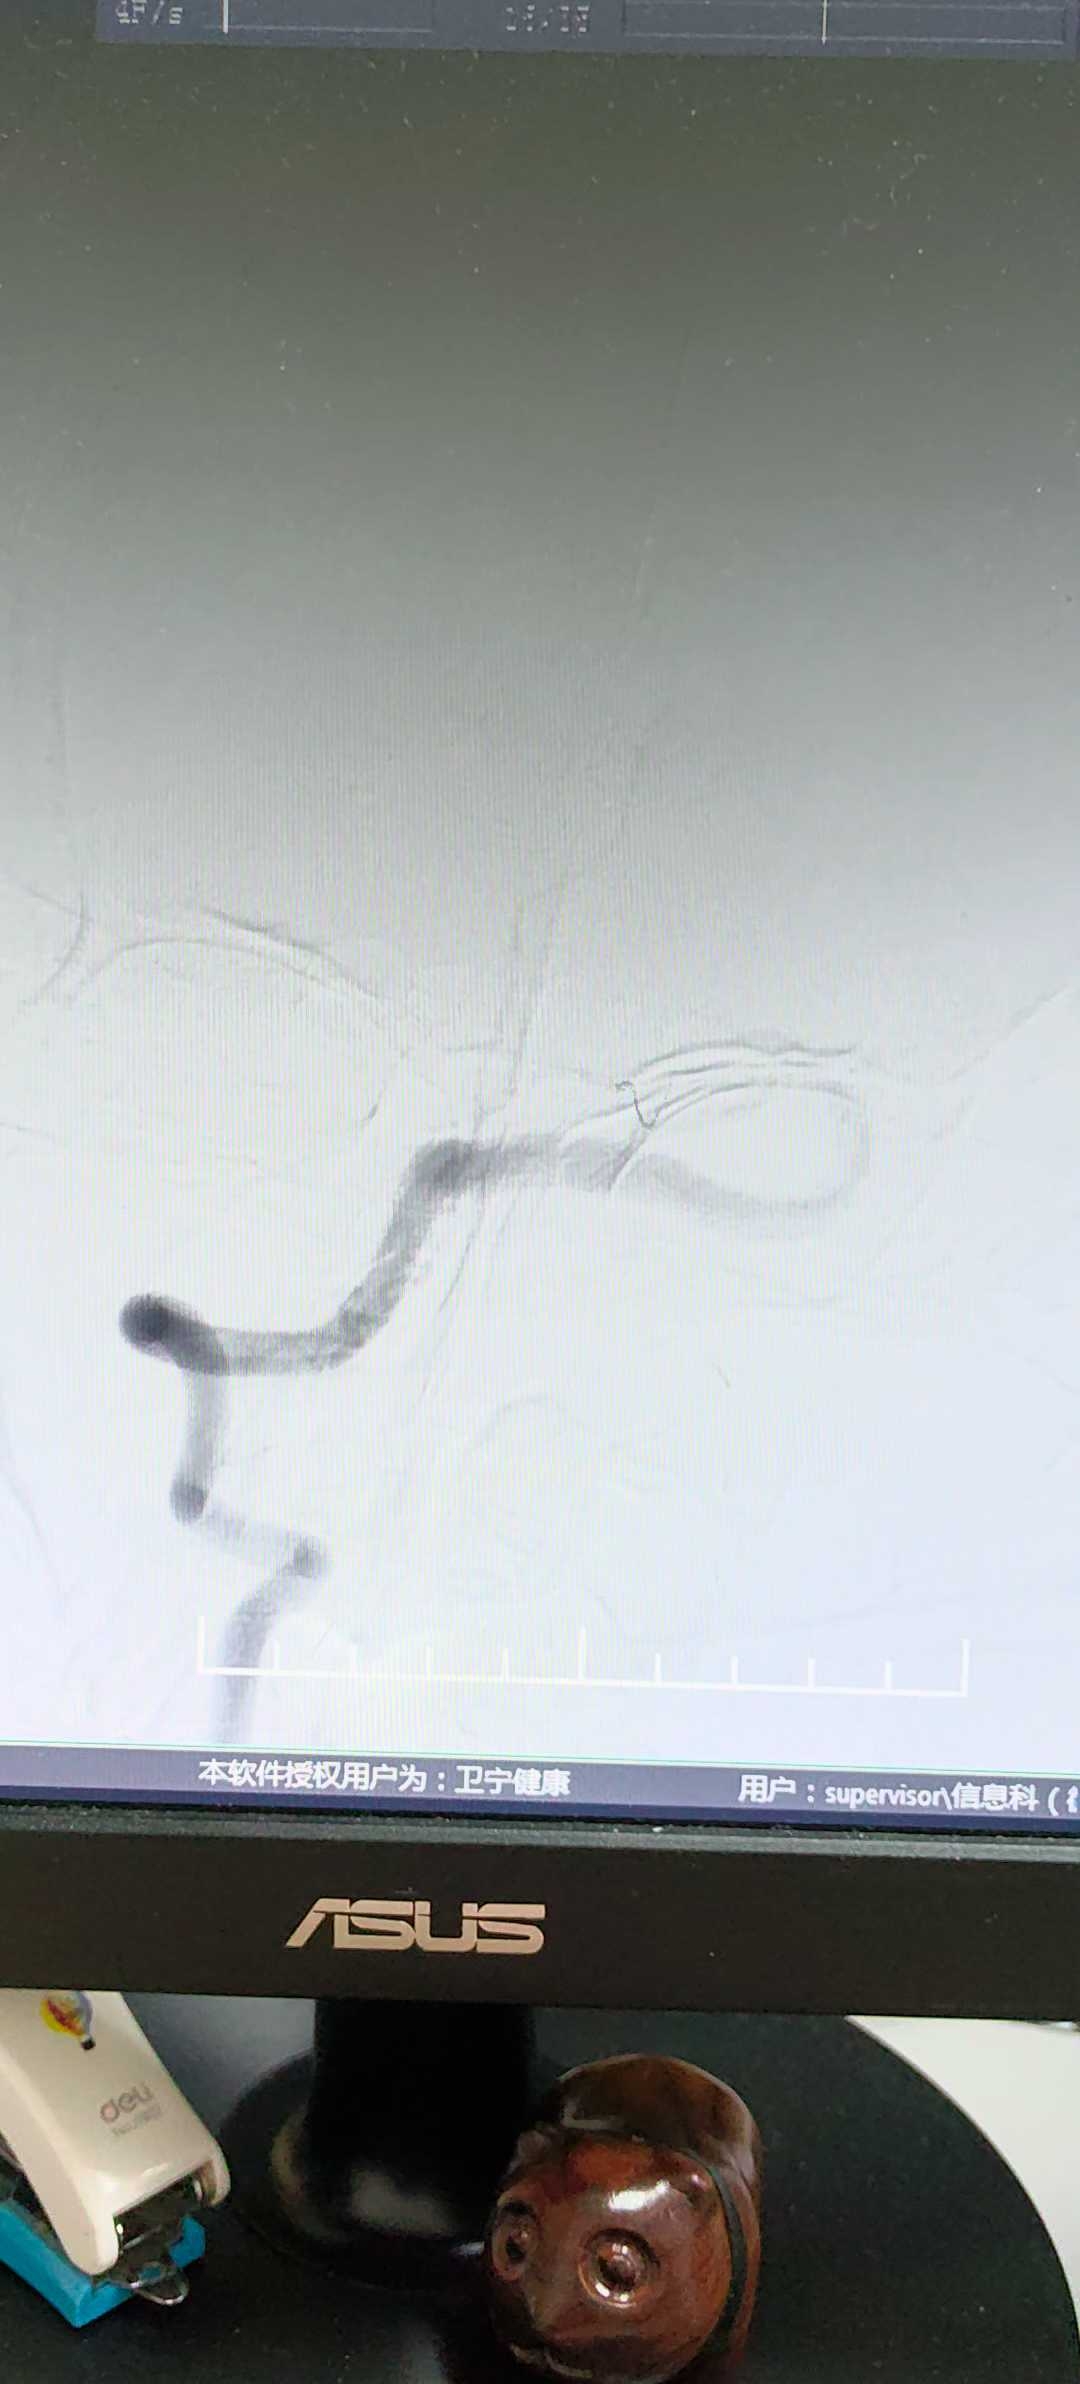

【患者信息】:男性,36岁

【主诉】:左侧肢体乏力1天

【现病史及既往史】:吸烟饮酒

【临床诊断】:基底动脉扩张延长

【治疗经过及结果】:抗血小板聚集稳定斑块治疗。